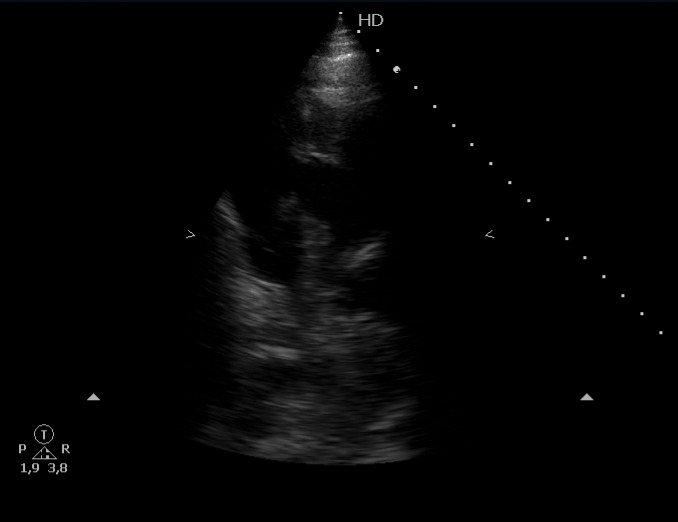

Escalas de riesgo probable para tromboembolismo pulmonar, cursando prueba de imagen que confirma patología y ampliando estudio con ecografía cardíaca que muestra presencia de émbolo intracardíaco.

Clasificación de trombo intracardíaco en Tipo A, B o C; el A tiene forma de gusano o serpiente, es móvil y suele asociarse a TVP.